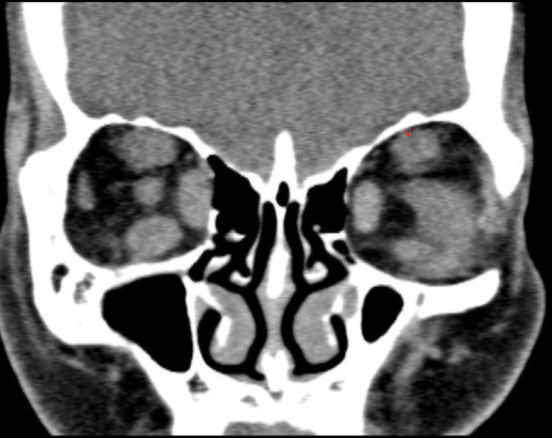

Hallazgos que podemos encontrar en una TC de orbitopatía tiroidea

• Agrandamiento de los músculos extraoculares

• Áreas de baja densidad debido a depósitos de glucosaminoglicano

• Exoftalmos

• Nervio óptico estirado

¿qué enfermedad sospechas?

orbitopatía tiroidea